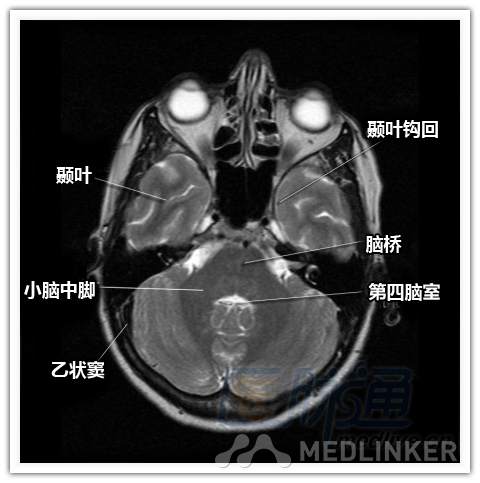

简明易懂的脑部断层解剖:横断位MRI(1)

本文将对不同横断位的脑部MRI图像进行标示,主要讲解内容是脑部基本解剖。脑部横断位解剖,尤其是内囊层面的影像学解剖一直是一大重点,一起来学习一下。 横断位图像顺序:由足侧至头侧 本文转载自医脉通。 声明:本文转载是出于提供更多信息以参考使用或学习、交流之目的,不用于商业用途。转载无意侵犯版权,如转载文章涉及您的权益等问题,请作者速来告知,我们将尽快做删除处理。